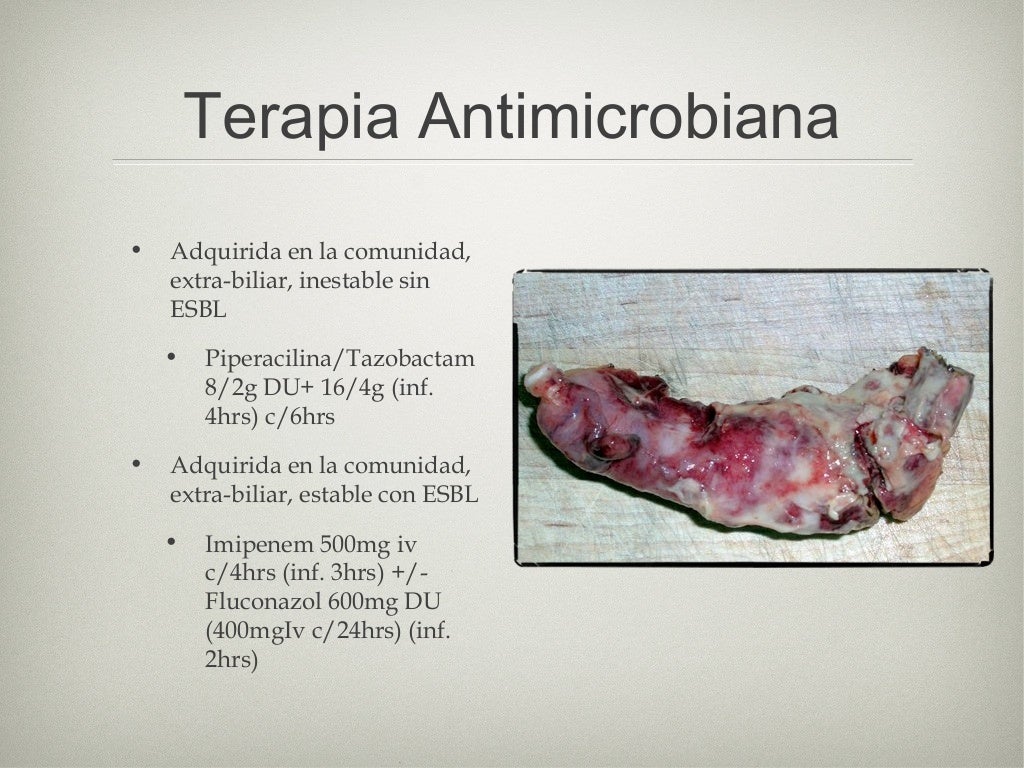

Sepsis abdominal fisiopatología, diagnóstico y tratamiento Medcmc